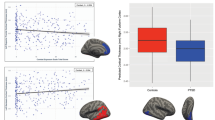

Exploratory analyses: symptom-tract associations

Symptom-tract associations were exploratory. Table 3 presents symptom-tract associations within the PTSD group (n = 31), analyzed by regression analyses, controlling for covariates (age and comorbidities). Notably, greater CAPS re-experiencing symptoms were significantly related to higher SFOF-FA (p = .031) and a borderline relationship to higher ACR-FA (p = .059). Neither tract was related to total CAPS scores. Interestingly, higher UF-FA was significantly associated with lower scores on GSI and mood disturbance, whereas higher SFOF-FA correlated with higher scores on GSI, mood disturbance, and dissociation (Fig. 3). The remaining tracts showed no significant relationships with symptoms. Comorbidities (loss of consciousness < 10 min and vascular disease) were significant predictors of higher SFOF-FA (all p’s < 0.05), independent of psychological symptoms.

Symptom-tract associations among veterans with PTSD. **p ≤ .01, *p ≤ .05. The data visualized is unadjusted and use the untransformed symptom scores for interpretability. The regression coefficients and p-values, given in each graph, are from full regression analyses that adjust for age and medical comorbidities (see Table 3)

It has been suggested that DSM diagnoses do not map on well to neurobiology, and should be complemented with dimensional investigations of specific symptoms (Insel 2014). Intriguingly, UF was consistently negatively associated with psychopathology symptoms (i.e., the SCL global severity index and mood disturbance subscales), whereas the SFOF was positively associated with symptoms of re-experiencing, dissociation and mood disturbance. While exploratory, these data raise the question of whether PTSD might be better understood through dimensional analyses of separate symptom clusters than as a categorical syndrome. While exploratory, these data raise the question of whether symptom-tract associations might reflect dissociable dimensions. Functional neuroimaging studies suggest that prototypical PTSD is associated with under-regulated affect (e.g., hypervigilance), whereas a “dissociative subtype” of PTSD has been associated with over-regulated affect (Lanius et al. 2010). However, the data visualizations in this study (Fig. 2) imply dimensional relationships. Future studies pairing structural and functional connectivity might elucidate whether different networks underlie the symptom expression of hyperarousal versus numbing/dissociation.